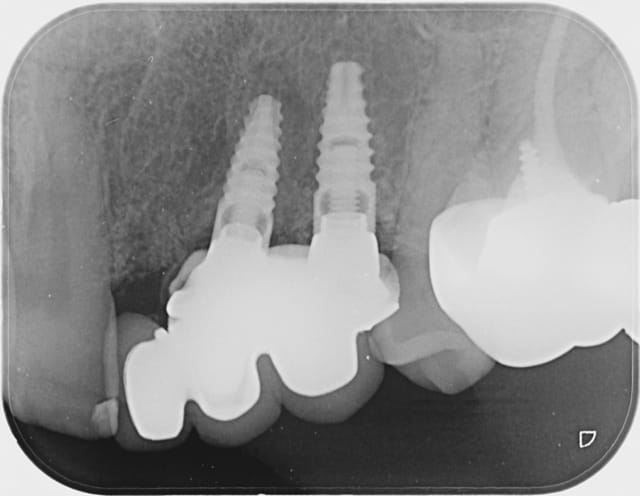

Les implants ou plutôt l'os autour semblent corrects sur la retroalveolaire donc pas le feu au lac.

Les implants n'ont pas l'air trop mal positionnés mais le boulot de prothèse je comprends vmt pas le projet :D.